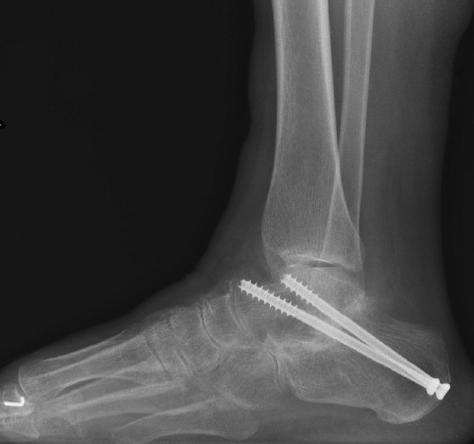

关节融合术仍然是治疗对保守治疗无效的疼痛性距下关节炎的金标准。其主要目标是实现疼痛缓解和恢复后足的力线。当关节炎只存在于距下关节时,对于保留后足运动,减少邻近关节炎发展的可能性,单纯距下关节融合术优于双重或三重关节融合术。单纯距下关节融合术已被证实可将距舟关节运动减少74%,跟骨运动减少44% 。从功能上讲,这导致完全失去了内翻/ 外翻; 然而,踝关节背屈和跖屈,以及通过横行的跖跗关节的部分内收和外展仍然保留。